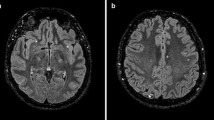

Other conditions such as occipital epilepsy can mimic migraine aura [78,79,80], although seizures tend to be shorter, occur in clusters, sometimes developing into temporal lobe or generalized epilepsy; however the differential diagnosis may be complicated by the fact that they can be accompanied by migrainous headache. Human neuroimaging depicting CSD-like phenomena in connection to seizures is lacking. The actual role of CSD in epilepsy is complex and obscure as data suggest that CSD can predispose to epileptic activity and vice-versa [81]. Migraine aura can be mistaken for a stroke [82, 83] as areas of hypoperfusion can be evidenced during migraine aura. Transient global amnesia (TGA), manifested as a transitory memory loss, could be a manifestation of hippocampal CSD, but may as well be due to a transient ischemic attack or a stroke, and abnormalities in diffusion weighted imaging can be observed due to either etiologies [84], rendering the differential diagnosis even more difficult.